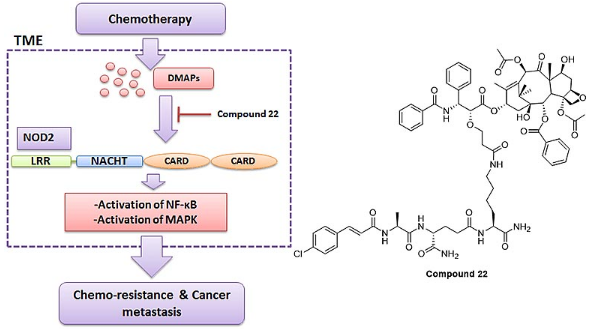

双靶点成功治疗多发性骨髓瘤

记者6月21日获悉���,南京传奇生物科技有限公司与西安交通大学第二附属医院合作展开的多靶点CAR-T疗法临床试验表现出惊人的客观缓解率,在近日举行的美国临床癌症学会年会上��,该疗法引起与会专家的高度评价和瞩目�。“患病后��,人体免疫细胞无法识别肿瘤细胞��,导致肿瘤快速复制转移病情扩散”���,南京传奇生物科技有限公司首席科学家兼创始人范晓虎说����,这种CAR-T疗法的特点是双靶点治疗,“目前大多数CAR-T疗法是一个靶点����,就像用一只手去抓球极易脱手,而双靶点相当于两只手去抓球����,成功率大大增加”。多发性骨髓瘤是三大血液系统恶性肿